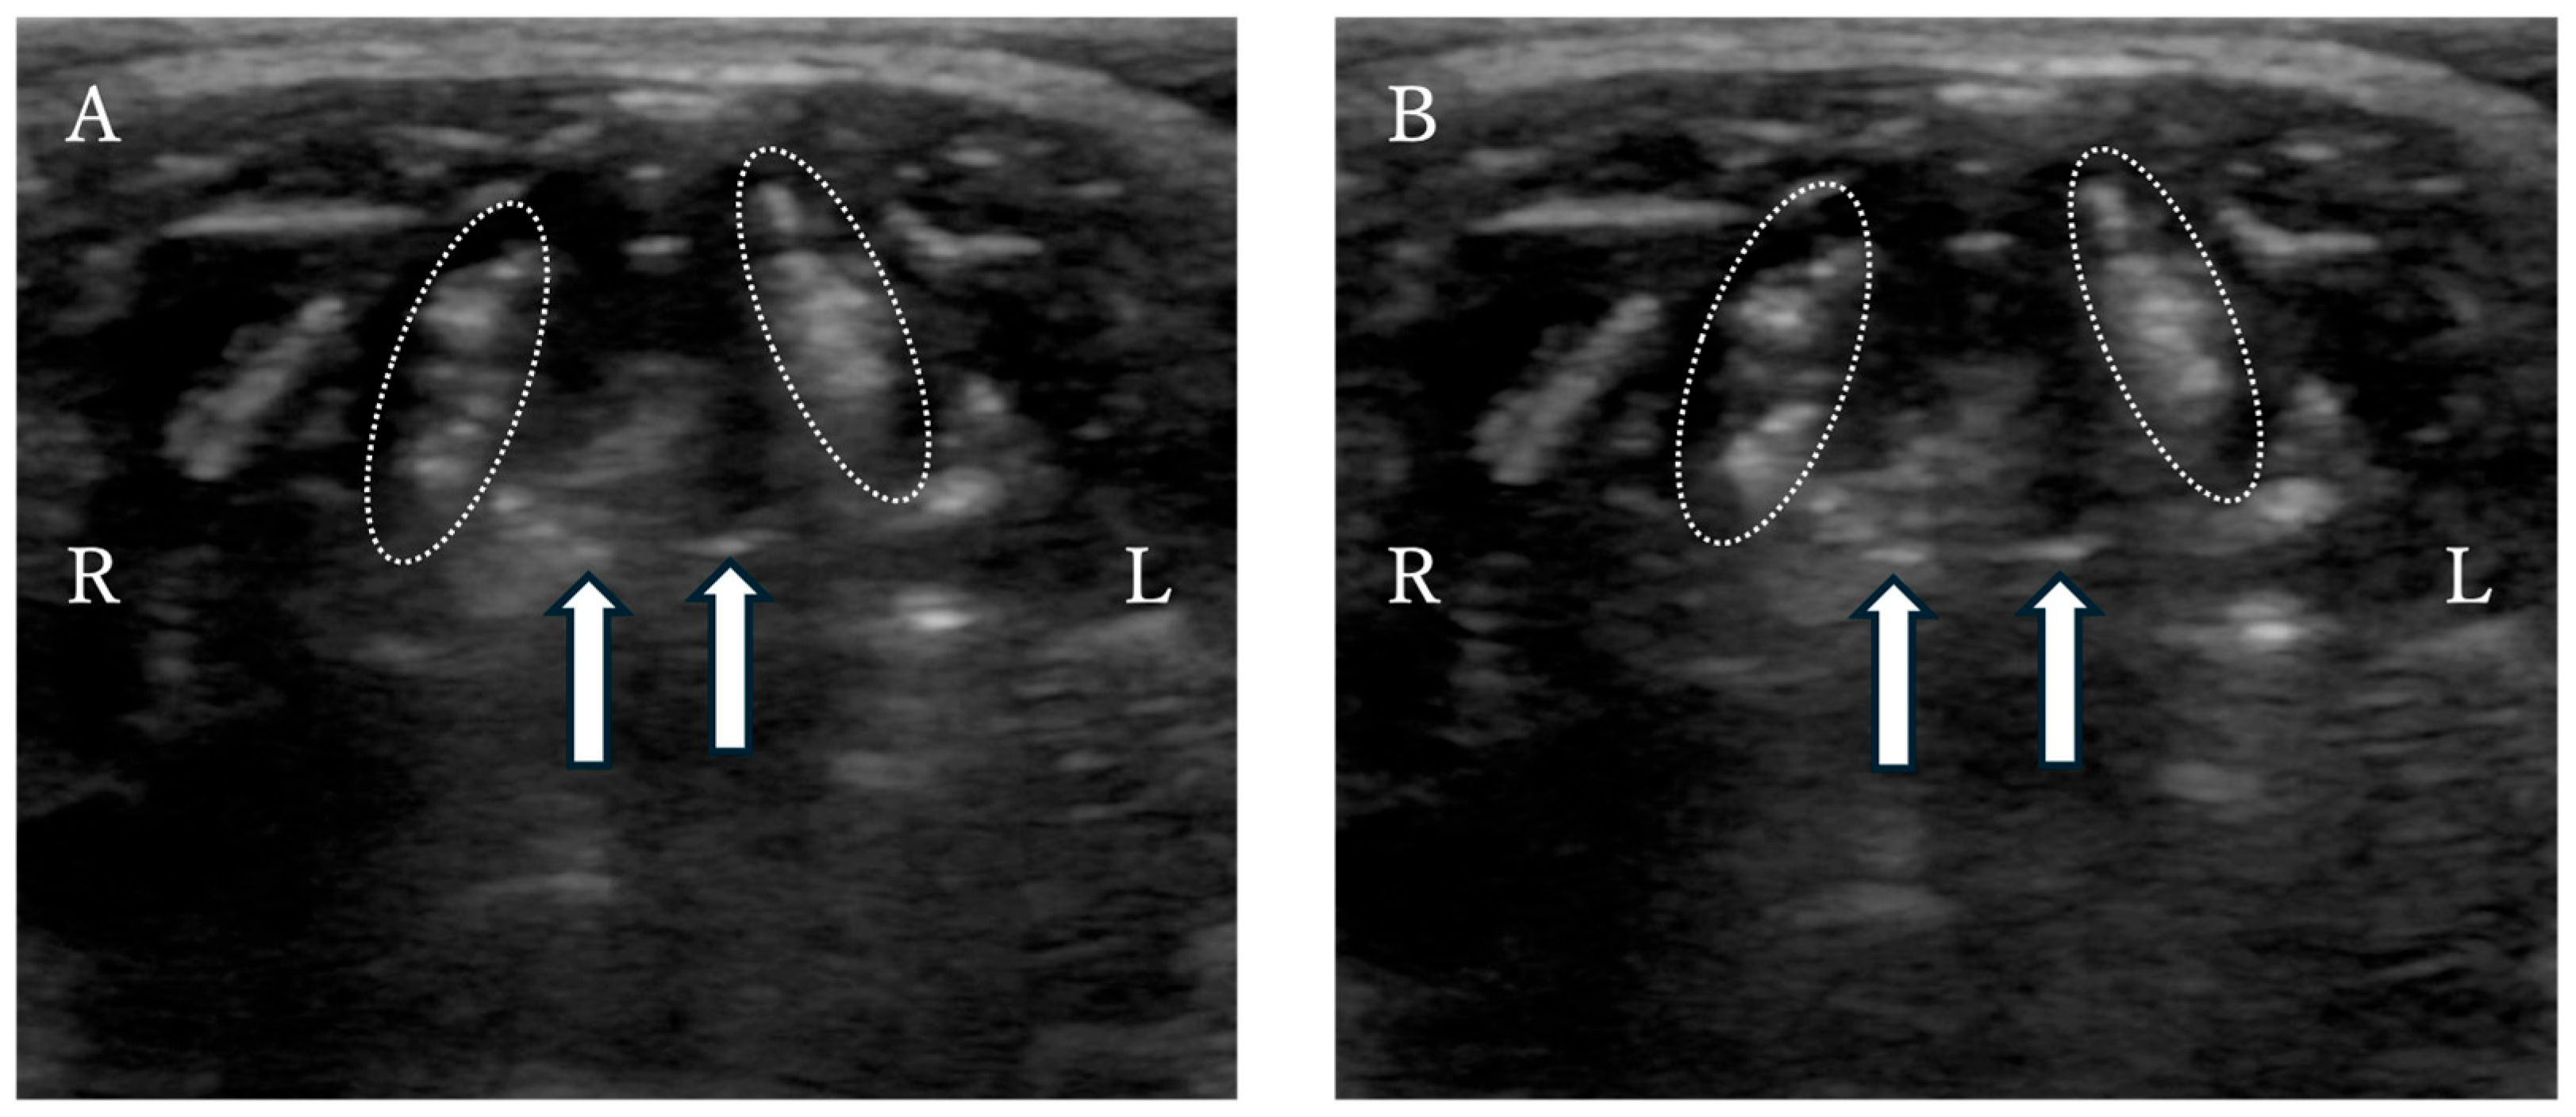

Seven days after discharge, the dog returned with inspiratory effort, cyanosis, and loss of vocalization. Radiography revealed no obvious abnormalities. Laryngeal ultrasound confirmed absence of motion of the cuneiform processes and caudal displacement of the whole larynx, leading to a diagnosis of laryngeal paralysis (Figure 5). Given that breathing was stable at rest and the owner declined anesthesia, medical management was chosen.

Figure 5. Laryngeal ultrasound of the dog revealed a lack of cuneiform process movement during (A) inspiration and (B) expiration. The dotted outline: the arytenoid cartilage. Arrows: cuneiform processes of the arytenoid cartilages.

Despite the unfavorable final outcome, this case suggests that conservative treatment may offer short-term symptomatic relief in selected dogs with suspected reversible laryngeal paralysis—particularly in individuals whose temperament maintains adequate rest. Nonetheless, this approach requires careful monitoring, as early identification of cases unlikely to improve is crucial to determine the appropriate timing for surgical intervention. In the dog, laryngeal ultrasound was used to assess suspected laryngeal paralysis. Although definitive diagnosis in dogs is typically achieved via laryngoscopy under mild sedation, the owner declined sedation; therefore, un-sedated ultrasonography was selected as the initial diagnostic modality [22]. Rudorf et al. (2001) reported that laryngeal ultrasound can accurately detect the presence and laterality of laryngeal paralysis [23]. In the present case, ultrasonography without anesthesia demonstrated an absence of cuneiform process motion and caudal displacement of the entire larynx. These findings were consistent with the characteristic ultrasonographic features described in previous paralysis cases [23]. Subsequent direct visualization during unilateral arytenoid lateralization confirmed the lack of arytenoid abduction during inspiration, thereby validating the ultrasound diagnosis. Laryngeal ultrasound offers several important advantages: it can be performed safely without sedation, poses minimal risk even in patients with severe respiratory distress, and allows real-time assessment of laryngeal motion [23]. It is particularly valuable when sedation is contraindicated or declined, as in the present case. Thus, this dog illustrates that laryngeal ultrasound provides sufficient diagnostic value for identifying laryngeal paralysis, even when standard sedated laryngoscopy cannot be performed. Overall, the dog illustrates the potential utility of PLLP as a supportive structure for managing tracheal stent fractures and highlights both the challenges and possible roles of conservative management in cases of postoperative laryngeal paralysis. The findings emphasize the need for further case accumulation to establish optimal criteria for device selection, appropriate surgical indications, and long-term outcomes.